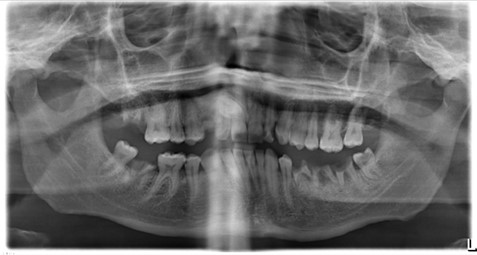

Radiographs taken Thursday, 25 May 2023

Justification: OPG was taken to assess progression of dental disease and support treatment planning under GA

Grade: diagnostically acceptable

Findings:

- Retained roots: UR7C, LLE67, LR7

- Periapical pathology associated with: UR7C, LLE67, LR7

- UR3 present

- UR6O, UR5M/D, UR4M/D, UL1D, UL2M/D, UL6O, LL8O, LR4D, LR6O radiolucencies consistent with caries

- Minimal generalised horizontal alveolar bone loss